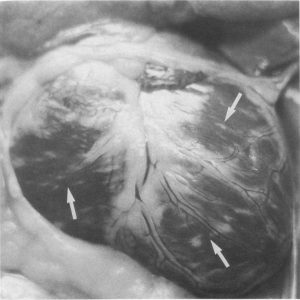

بی حالی. از دست دادن اشتها، درد شکم و نفخ، تب یا دمای پایین بدن (هیپوترمی)، استفراغ، اسهال شدید( اغلب خونی، بد بو و مداوم)، استفراغ و که می تواند باعث کم آبی سریع بدن شود همچنین آسیب به روده ها و سیستم ایمنی بدن می تواند باعث شوک سپتیک شود. ممکن است میوکاردیت CPV، با رگه های رنگ پریده در میوکارد دیده شود.

علائم کلینیکی و کالبدگشائی عفونت پاروویروسی در سگ از نگاه تصویر